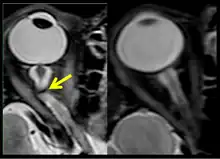

The sixth case of visual changes of an ISS astronaut was reported after return to Earth from a 6-month mission. When he noticed that his far vision was clearer through his reading glasses. A fundus examination performed 3 weeks postflight documented a grade 1 nasal optic-disc edema in the right eye only. There was no evidence of disc edema in the left eye or choroidal folds in either eye (Figure 13). MRI of the brain and eyes days postflight revealed bilateral flattening of the posterior globe, right greater than left, and a mildly distended right optic nerve sheath. There was also evidence of optic-disc edema in the right eye. A fundus examination postflight revealed a "new onset" cotton-wool spot in the left eye. This was not observed in the fundus photographs taken 3 weeks postflight.[5]

The seventh case of visual changes associated with spaceflight is significant in that it was eventually treated postflight. Approximately 2 months into the ISS mission, the astronaut reported a progressive decrease in his near and far acuity in both eyes. The ISS cabin pressure, CO2 and O2 levels were reported to be within normal operating limits and the astronaut was not exposed to any toxic substances. He never experienced losses in subjective best-corrected acuity, color vision or stereopsis. A fundus examination revealed a grade 1 bilateral optic-disc edema and choroidal folds (Figure 15).[5]